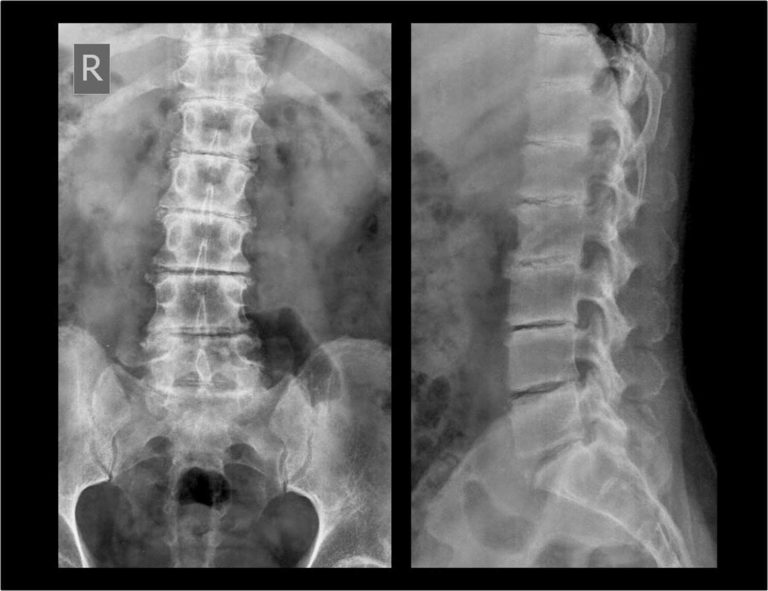

from radiopaedia.org

Lumbosacral spine radiography AP and lateral views showing lumbar What Is Lumbosacral Spine X-Ray This area includes the lumbar region and the sacrum, the area that connects the spine to. It takes pictures of the 5 bones of the lower back (lumbar vertebrae) and a view of the 5 fused bones at the bottom of the. Abnormal wear on the cartilage and bones of the lower. It can help your doctor find out what's. What Is Lumbosacral Spine X-Ray.